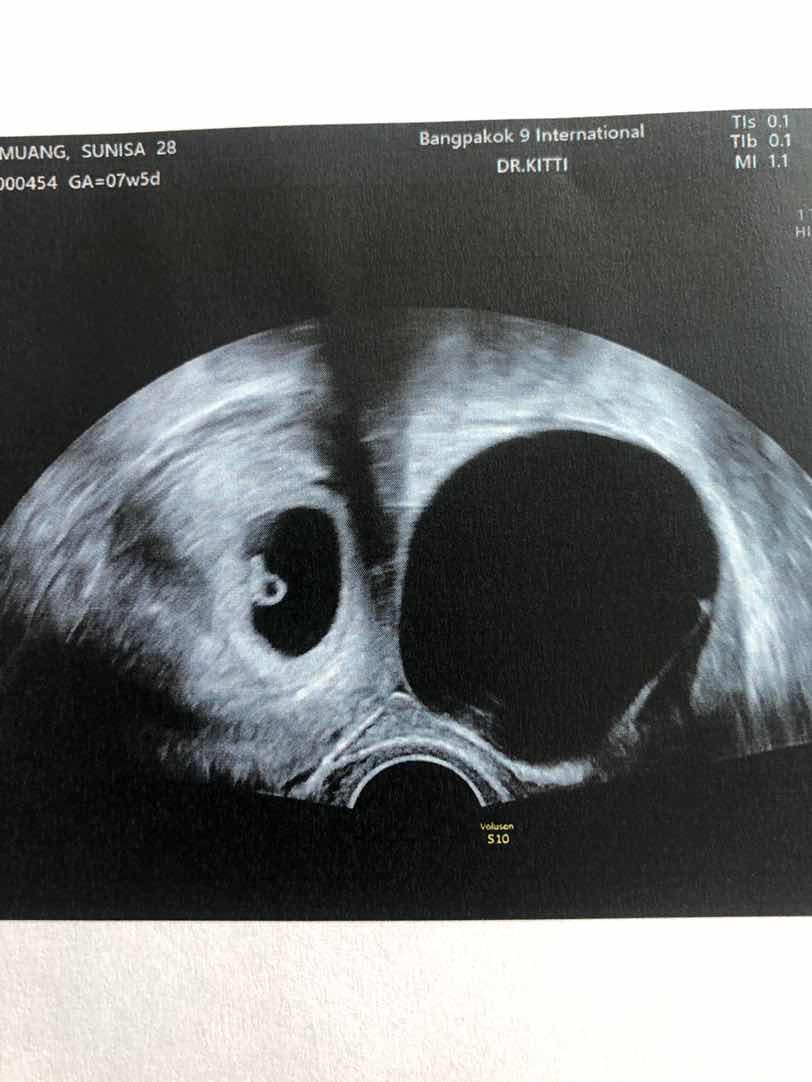

ท้องได้ 8 สัปดาห์ 2 วัน แต่มีถุงน้ำด้านซ้าย 6 เซนติเมตร

วันนี้ไปหาหมอไปซาวดูเด็ก แต่พบถุงน้ำนอกมดลูก 6 เซนติเมตร ไม่รู้ว่าต้องรักษายังไง ทำตัวแบบไหนบ้างหมอบอกแค่ว่านัดตรวจอีกที ถ้าปวดมาก ต้องผ่าตัดอาจเสียเด็กไป ซึ่งมันน่าเศร้าใจมาก เครียดมาก เพราะเราตัดปีกข้างขวาไปแล้ว ตัดอีกเราก็ไม่สามารถมีได้อีกเลย ใครมีคำแนะนำอะไรบอกได้นะคะ ช็อคมากคะ

คุณแม่มีทั้งถุงตั้งครรภ์ในมดลูก แล้วก็ถุงน้ำที่ปีกมดลูก 6 ซม ใช่มั้ยคะ ถ้าเป็นอย่างนั้นก็อย่าเพิ่งกังวลไปค่ะ ถุงน้ำมีโอกาสเล็กลงได้อยู่ ช่วงนี้ก็คอยสังเกตุอาการปวดท้องตามที่หมอบอก ถ้าท้องเลย 3 เดือนไปความเสี่ยงที่จะต้องผ่าก็น่าจะลดลงค่ะ